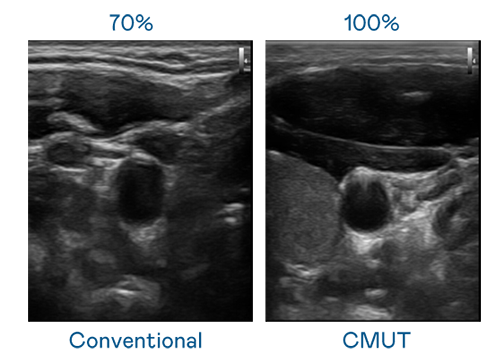

CMUT 技术是一种用电容式微机电元件来产生超音波讯号的技术。与传统 PZT 压电式技术相比,CMUT 频宽增加 30%,更宽频的超音波讯号让影像解析度大幅提升,是实现高影像品质医疗超音波扫描、促进精准医疗发展的关键技术。

大频宽带来超清晰影像

超音波影像的解析度高低,首先取决于探头能发出的讯号频宽。88BIFA CMUT 可提供高清晰的超音波讯号,提供高频宽、高灵敏度、影像纹理细节更高的超音波影像,协助医护人员缩短影像判读时间及利用精准的医疗影像进行诊断。